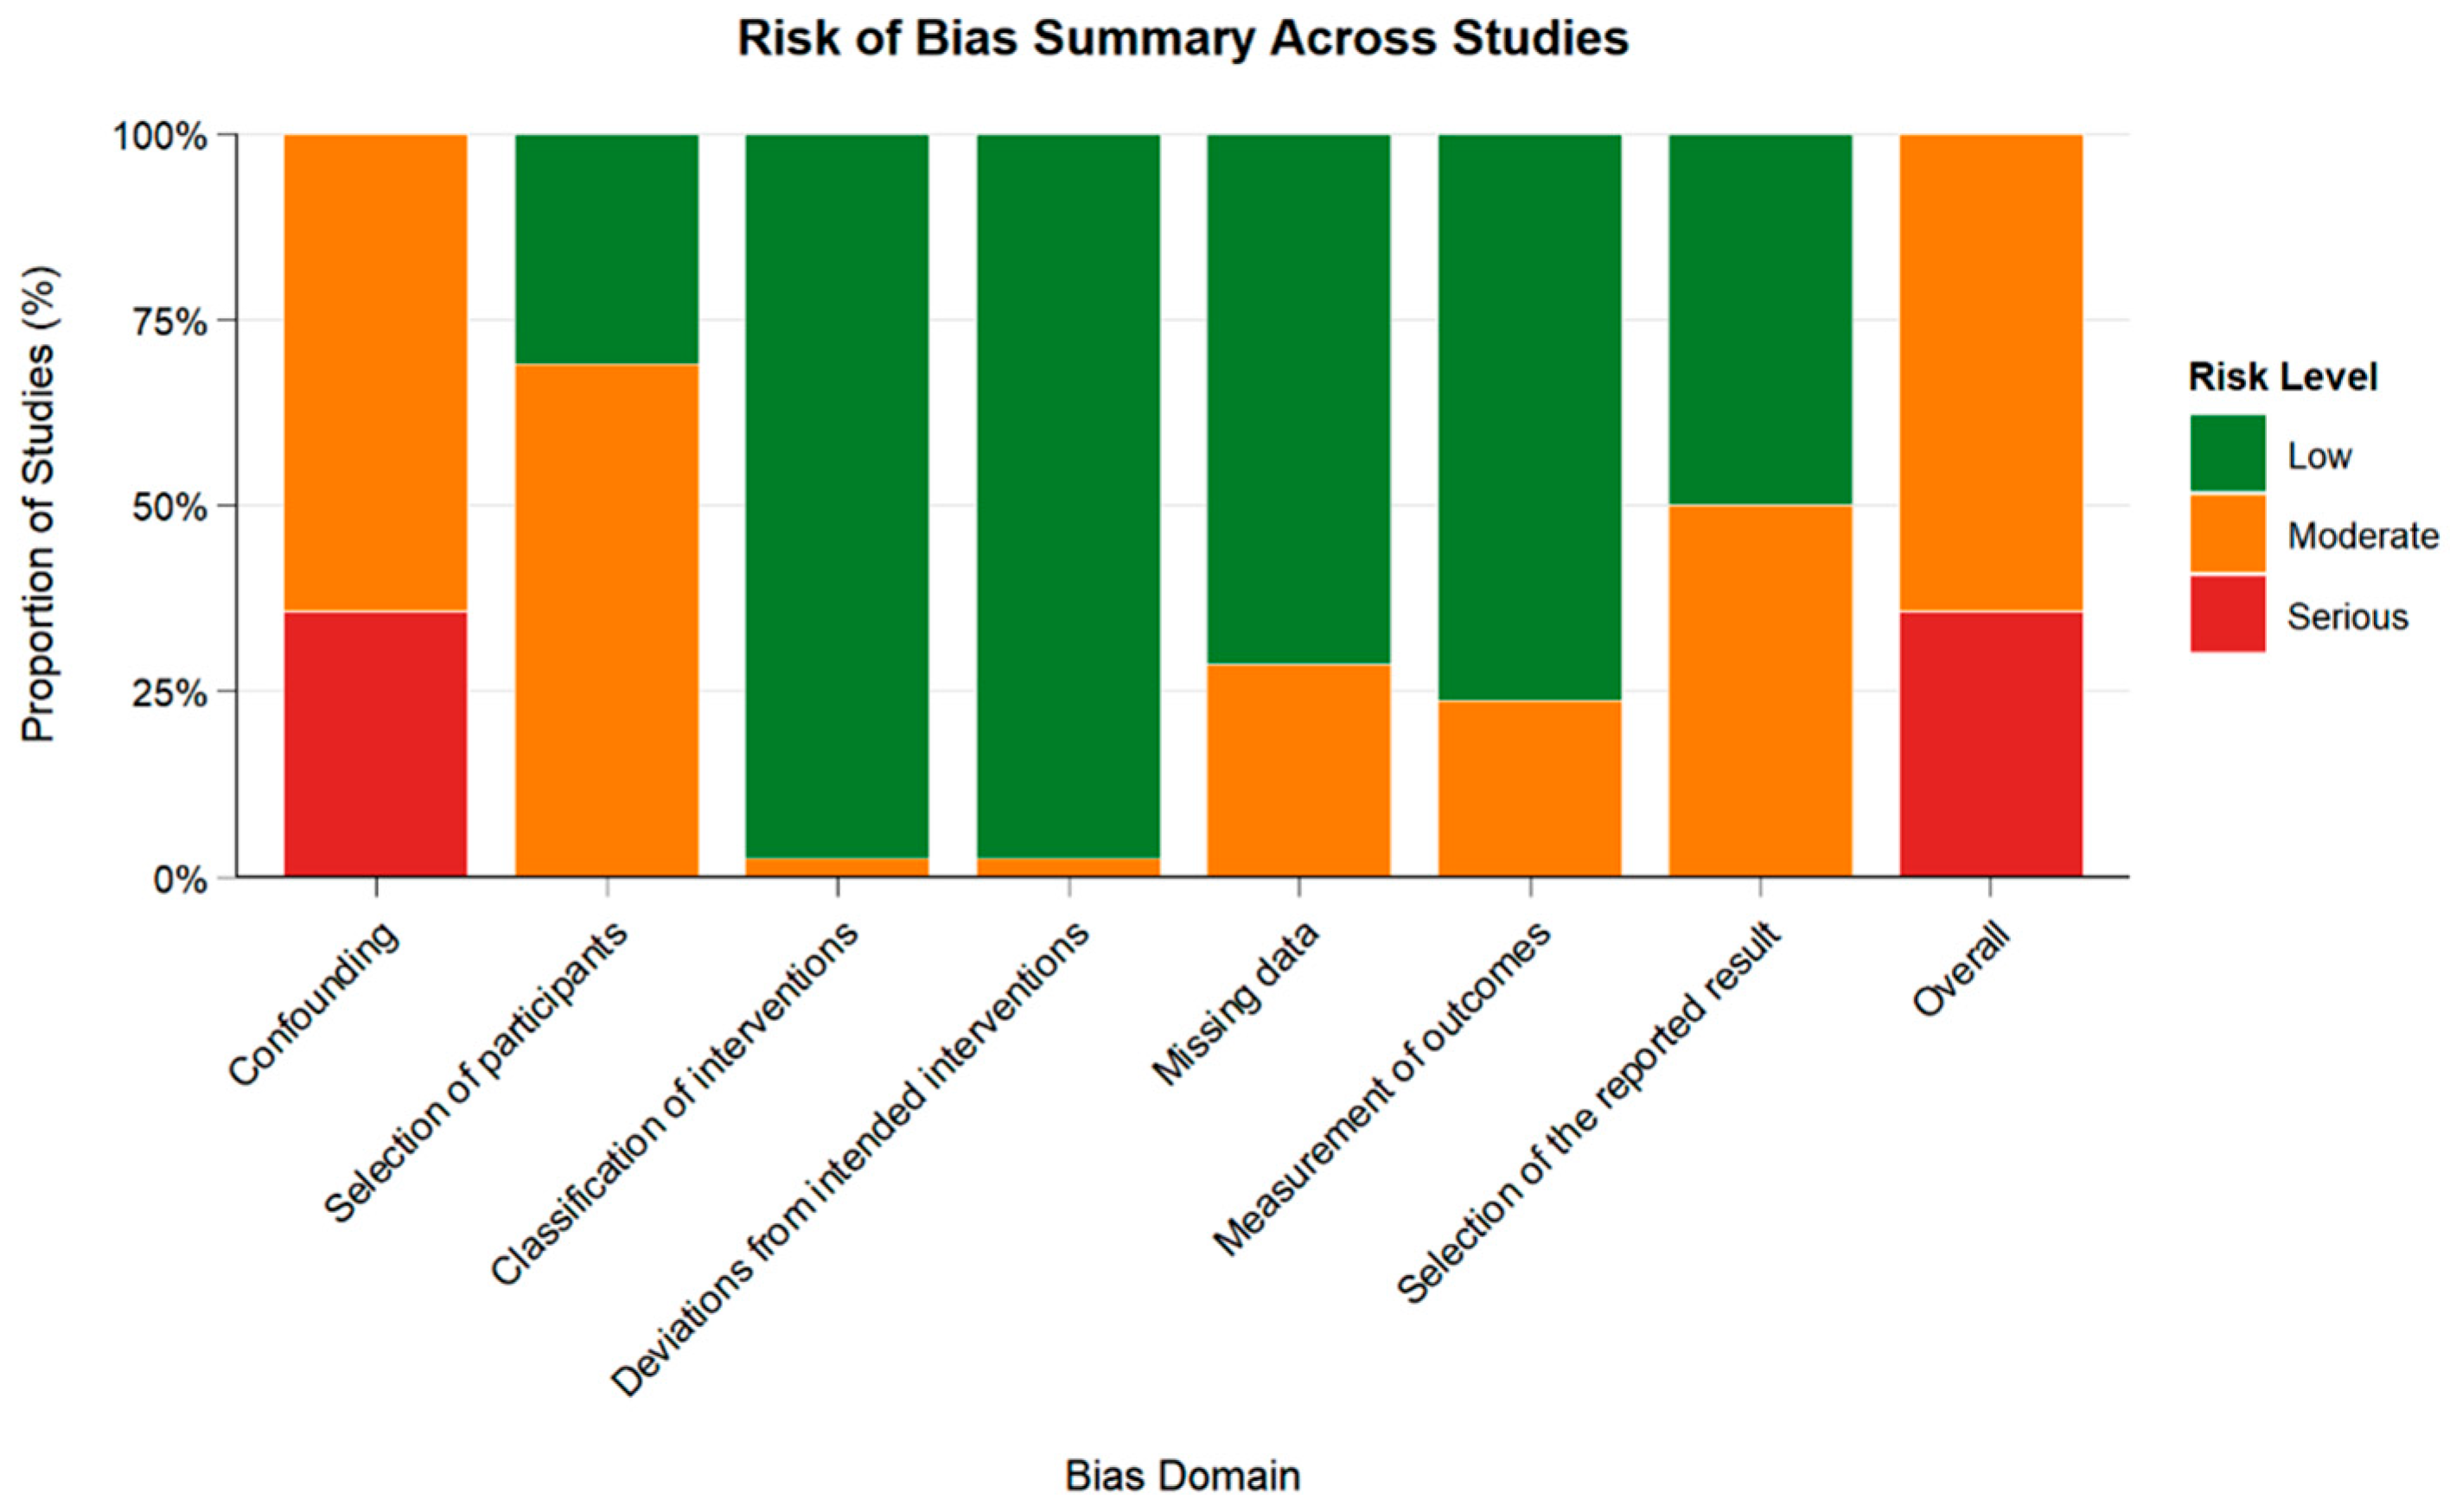

3.2.2. Risk of Bias Assessment